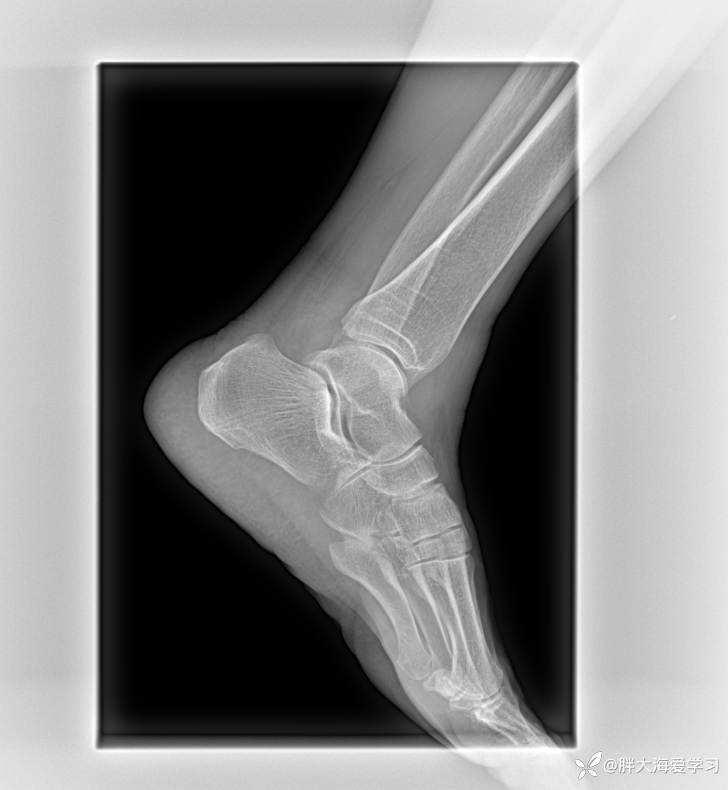

反复左侧踝关节肿胀疼痛 4 月余

患者 4 月前无明显诱因出现左侧踝关节肿胀疼痛,活动受限,期间反复发作四次,均在我院治疗,治疗给予电针、中频脉冲、中药封包、小针刀治疗、(倍他米松注射液、维生素 B12 注射液、利多卡因注射液行关节腔注射),但每次都只能维持半个月左右就会发作,类风湿因子、抗 O、C 反应蛋白均正常,